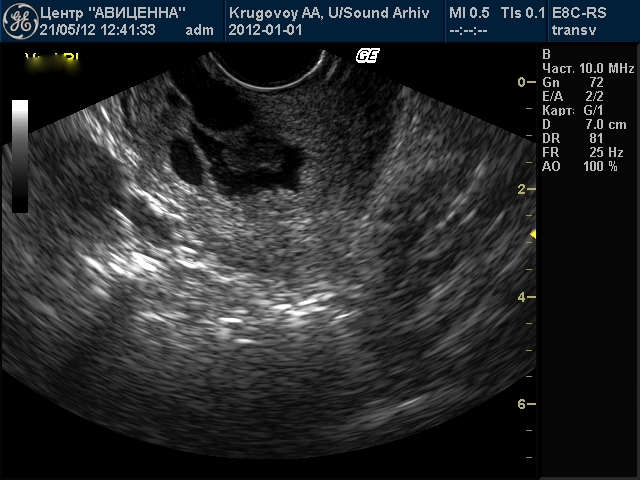

Можно ли на узи увидеть кисту на шейке матки - фото презентация